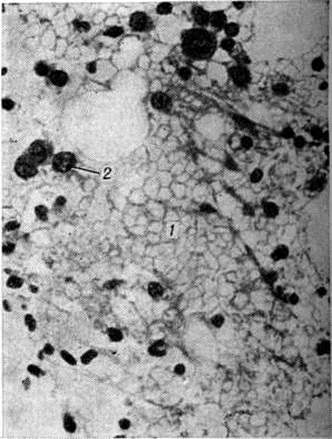

Острый миелобластный лейкоз в развёрнутой стадии болезни характеризуется выраженной лейкозной инфильтрацией костного мозга и других органов. В печени лейкозные разрастания локализуются в синусоидных капиллярах и в области портальных трактов. Аналогичное расположение инфильтратов имеется и при других более редких формах острого Лейкозы (монобластном, миеломонобластном, недифференцируемом, промиелоцитарном и другие), поэтому данный признак не может служить основанием для разграничения форм острого Лейкозы В лёгких лейкозная инфильтрация обычно выявляется по ходу межальвеолярных перегородок с выходом бластных клеток в просветы альвеол (рисунок 3), возможна локализация и в окружности бронхов, сосудов, междольковых перегородках. У детей при этой форме Лейкозы лейкозные разрастания в вилочковой железе располагаются в соединительнотканных прослойках, сдавливают дольки, что сопровождается увеличением количества аргирофильных волокон. У взрослых типично развитие множественных узлов в надкостнице плоских и трубчатых костей, почках, печени, половых железах, жировой клетчатке (подкожной, ретробульбарной, клетчатке большого сальника и малого таза), иногда в коже, конъюнктиве, твёрдой мозговой оболочке и костном мозге. В ряде случаев в области опухолевых узлов и системных поражений имеется зелёное окрашивание ткани (хлоролейкоз). Аналогичные изменения могут выявляться и при Лейкозы у детей.

При микроскопическом исследовании в костном мозге преобладают незрелые и зрелые клетки гранулоцитарного ряда (рисунок 5), соотношение которых может варьировать. По данным трепанобиопсий, в начальной стадии заболевания ещё в достаточном количестве сохраняются элементы эритропоэтического и мегакариоцитарного ряда. По мере прогрессирования процесса их число снижается, исчезают жировые клетки. Характерны глубокие изменения в строме в виде сочетания процессов деструкции с увеличением количества фибробластов, аргирофильных и иногда коллагеновых волокон. Изучение костного мозга методом трепанобиопсии в динамике свидетельствует о том, что миелофиброз постепенно нарастает и бывает более выражен у больных с повторными ремиссиями и обострениями заболевания. В отдельных случаях в костном мозге имеют место обширные очаги некроза; постоянно наблюдается выраженное рассасывание костной ткани. В селезёнке и лимфатических узлах в развёрнутой стадии болезни обнаруживается диффузная инфильтрация миелоидными элементами, атрофия лимфатической ткани. Лейкозное поражение селезёнки часто сопровождается выраженным в различной степени фиброзом красной пульпы, образованием полей склероза, что наряду с инфильтрацией и полнокровием является причиной увеличения её веса. Для хронический миелолейкоза характерна локализация лейкозных инфильтратов в печени по ходу синусоидных капилляров (рисунок 6), в лёгких — в области межальвеолярных перегородок. Нередко наблюдается инфильтрация стенок мелких бронхов, сосудов, плевры. Реже, чем при острых Лейкозы очаги лейкозной инфильтрации возникают в почках, мышце сердца, в стенках желудочно-кишечные тракта, в оболочках и веществе головного мозга, коже, железах внутренней секреции и других органах.

Микроскопически в костном мозге обнаруживается системное разрастание лимфоцитов. При обострении процесса наряду со зрелыми лимфоцитами выявляются пролимфоциты и лимфобласты. В костном мозге выделяют три типа инфильтрации: диффузную, диффузно-очаговую, очаговую. При первых двух типах инфильтрации расширенные полости костного мозга содержат значительное количество лимфоцитов, диффузно рассеянных в ткани или образующих наряду с этим компактные скопления (диффузно-очаговый тип). В отличие от других форм Лейкозы даже при массивной инфильтрации в костном мозге сохраняются небольшие очаги нормального кроветворения, не исчезают полностью жировые клетки. Для хронический лимфолейкоза характерно резкое рассасывание костной ткани и отсутствие признаков её новообразования. Данные прижизненного гистологический исследования костного мозга показывают, что очаговый тип инфильтрации наблюдается в ранние стадии заболевания. В отличие от лимфоидных узелков, выявляемых в норме в костном мозге, а также от реактивной нодулярной лимфоидной гиперплазии, сопутствующей ряду заболеваний, при хронический лимфолейкозе очаговые скопления лимфоцитов характеризуются довольно крупными размерами, лишены чётких границ, имеют тенденцию к слиянию, содержат наряду со зрелыми лимфоцитами пролимфоциты и лимфобласты. Разграничение этих изменений с метастазами в костный мозг лимфоцитарной лимфосаркомы ввиду сходности морфологический картины основывается на особенностях клинические, проявлений заболевания. При развёрнутой картине хронический лимфолейкоза в лимфатических, узлах обнаруживается диффузная инфильтрация ткани лимфоцитами с полным стиранием рисунка, которая может проникать через капсулу в окружающую жировую клетчатку. В селезёнке в некоторых случаях видны резко увеличенные в размерах фолликулы без центров размножения, сливающиеся друг с другом, однако чаще имеется полное стирание рисунка вследствие диффузной инфильтрации ткани лимфоцитами. Нередко встречаются поля склероза. В печени обширные скопления лимфатических, клеток располагаются главным образом в области портальных полей (рисунок 7), но могут встречаться и в синусоидных капиллярах. В зонах инфильтрации нередко имеет место разрастание аргирофильных и коллагеновых волокон. Часто наблюдается расширение желчных капилляров и застой желчи, дистрофия, частичный некробиоз и некроз гепатоцитов. В лёгких разрастания локализуются в стенках бронхов, что приводит к нарушению их дренажной функции и способствует развитию пневмоний. Могут наблюдаться участки массивной лейкозной инфильтрации ткани лёгкого. При микроскопии гнездные скопления лимфоцитов нередко обнаруживаются в строме почек, оболочках и мышце сердца, половых железах, жировой клетчатке и так далее. Очень редко встречается специфическая инфильтрация оболочек и вещества головного мозга. Частой находкой является скопление лимфоцитов в просветах сосудов различных органов, особенно при значительном лейкоцитозе. В отдельных случаях при обострении хронический лимфолейкоза возникают массивные опухолевые разрастания, исходящие главным образом из лимфатических, узлов. Опухолевые массы состоят из крупных недифференцированных клеток с уродливыми ядрами, нередко в них обнаруживаются участки некроза, кровоизлияния. Характерен резко выраженный инфильтрирующий рост.